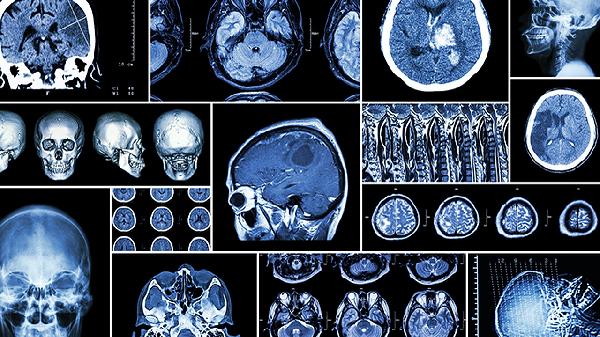

先天性脑血管畸形如动脉瘤、动静脉瘘等病变,在老年期更易因血流动力学改变而破裂。部分患者可能前期有短暂性脑缺血发作史。确诊需依赖脑血管造影检查,必要时可行介入栓塞治疗。